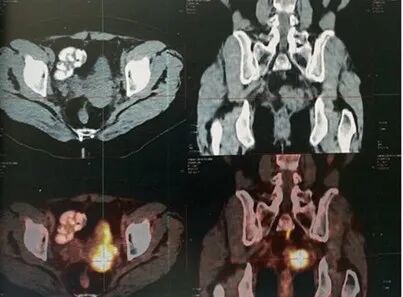

MRI:阴道残端复发,累及膀胱、左侧输尿管下段、左侧盆壁、乙状结肠及局部直肠系膜及筋膜;左侧输尿管中上段梗阻性扩张。

PET-CT:盆腔内左侧团块状软组织密度影,累及膀胱左后壁及左侧输尿管下段。